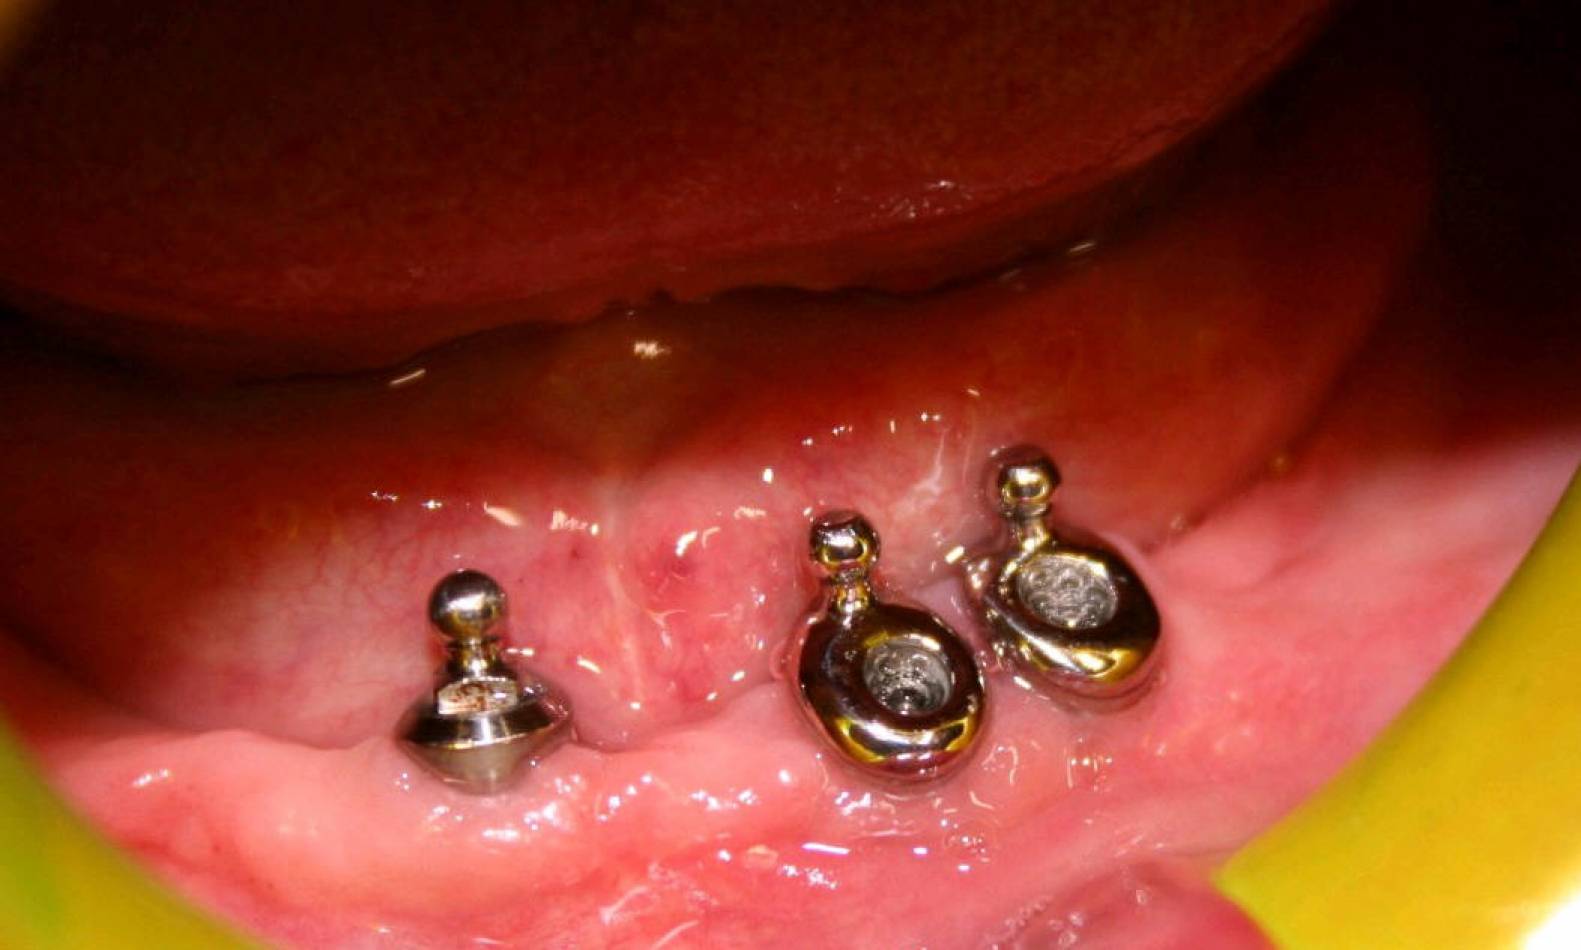

Implantologia e Chirurgia

Si effettua implantologia con impianti STRAUMANN e tecnologia IDI EVOLUTION.